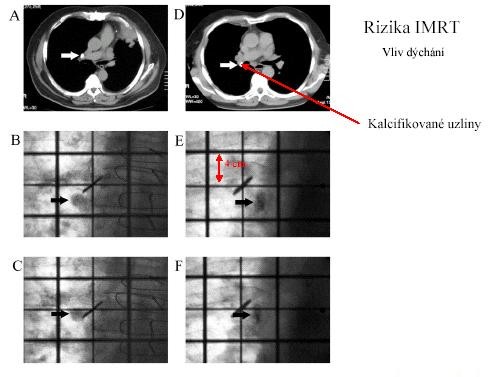

Rizika IMRT

Vliv dýchání

Nastavení

Pohyb orgánů

- dýchání

- pohyb stejnostranné HK

- změna objemu prsu v průběhu ozařování (až 10%)

Nepřesnost nastavení (comfort pozice, věk)